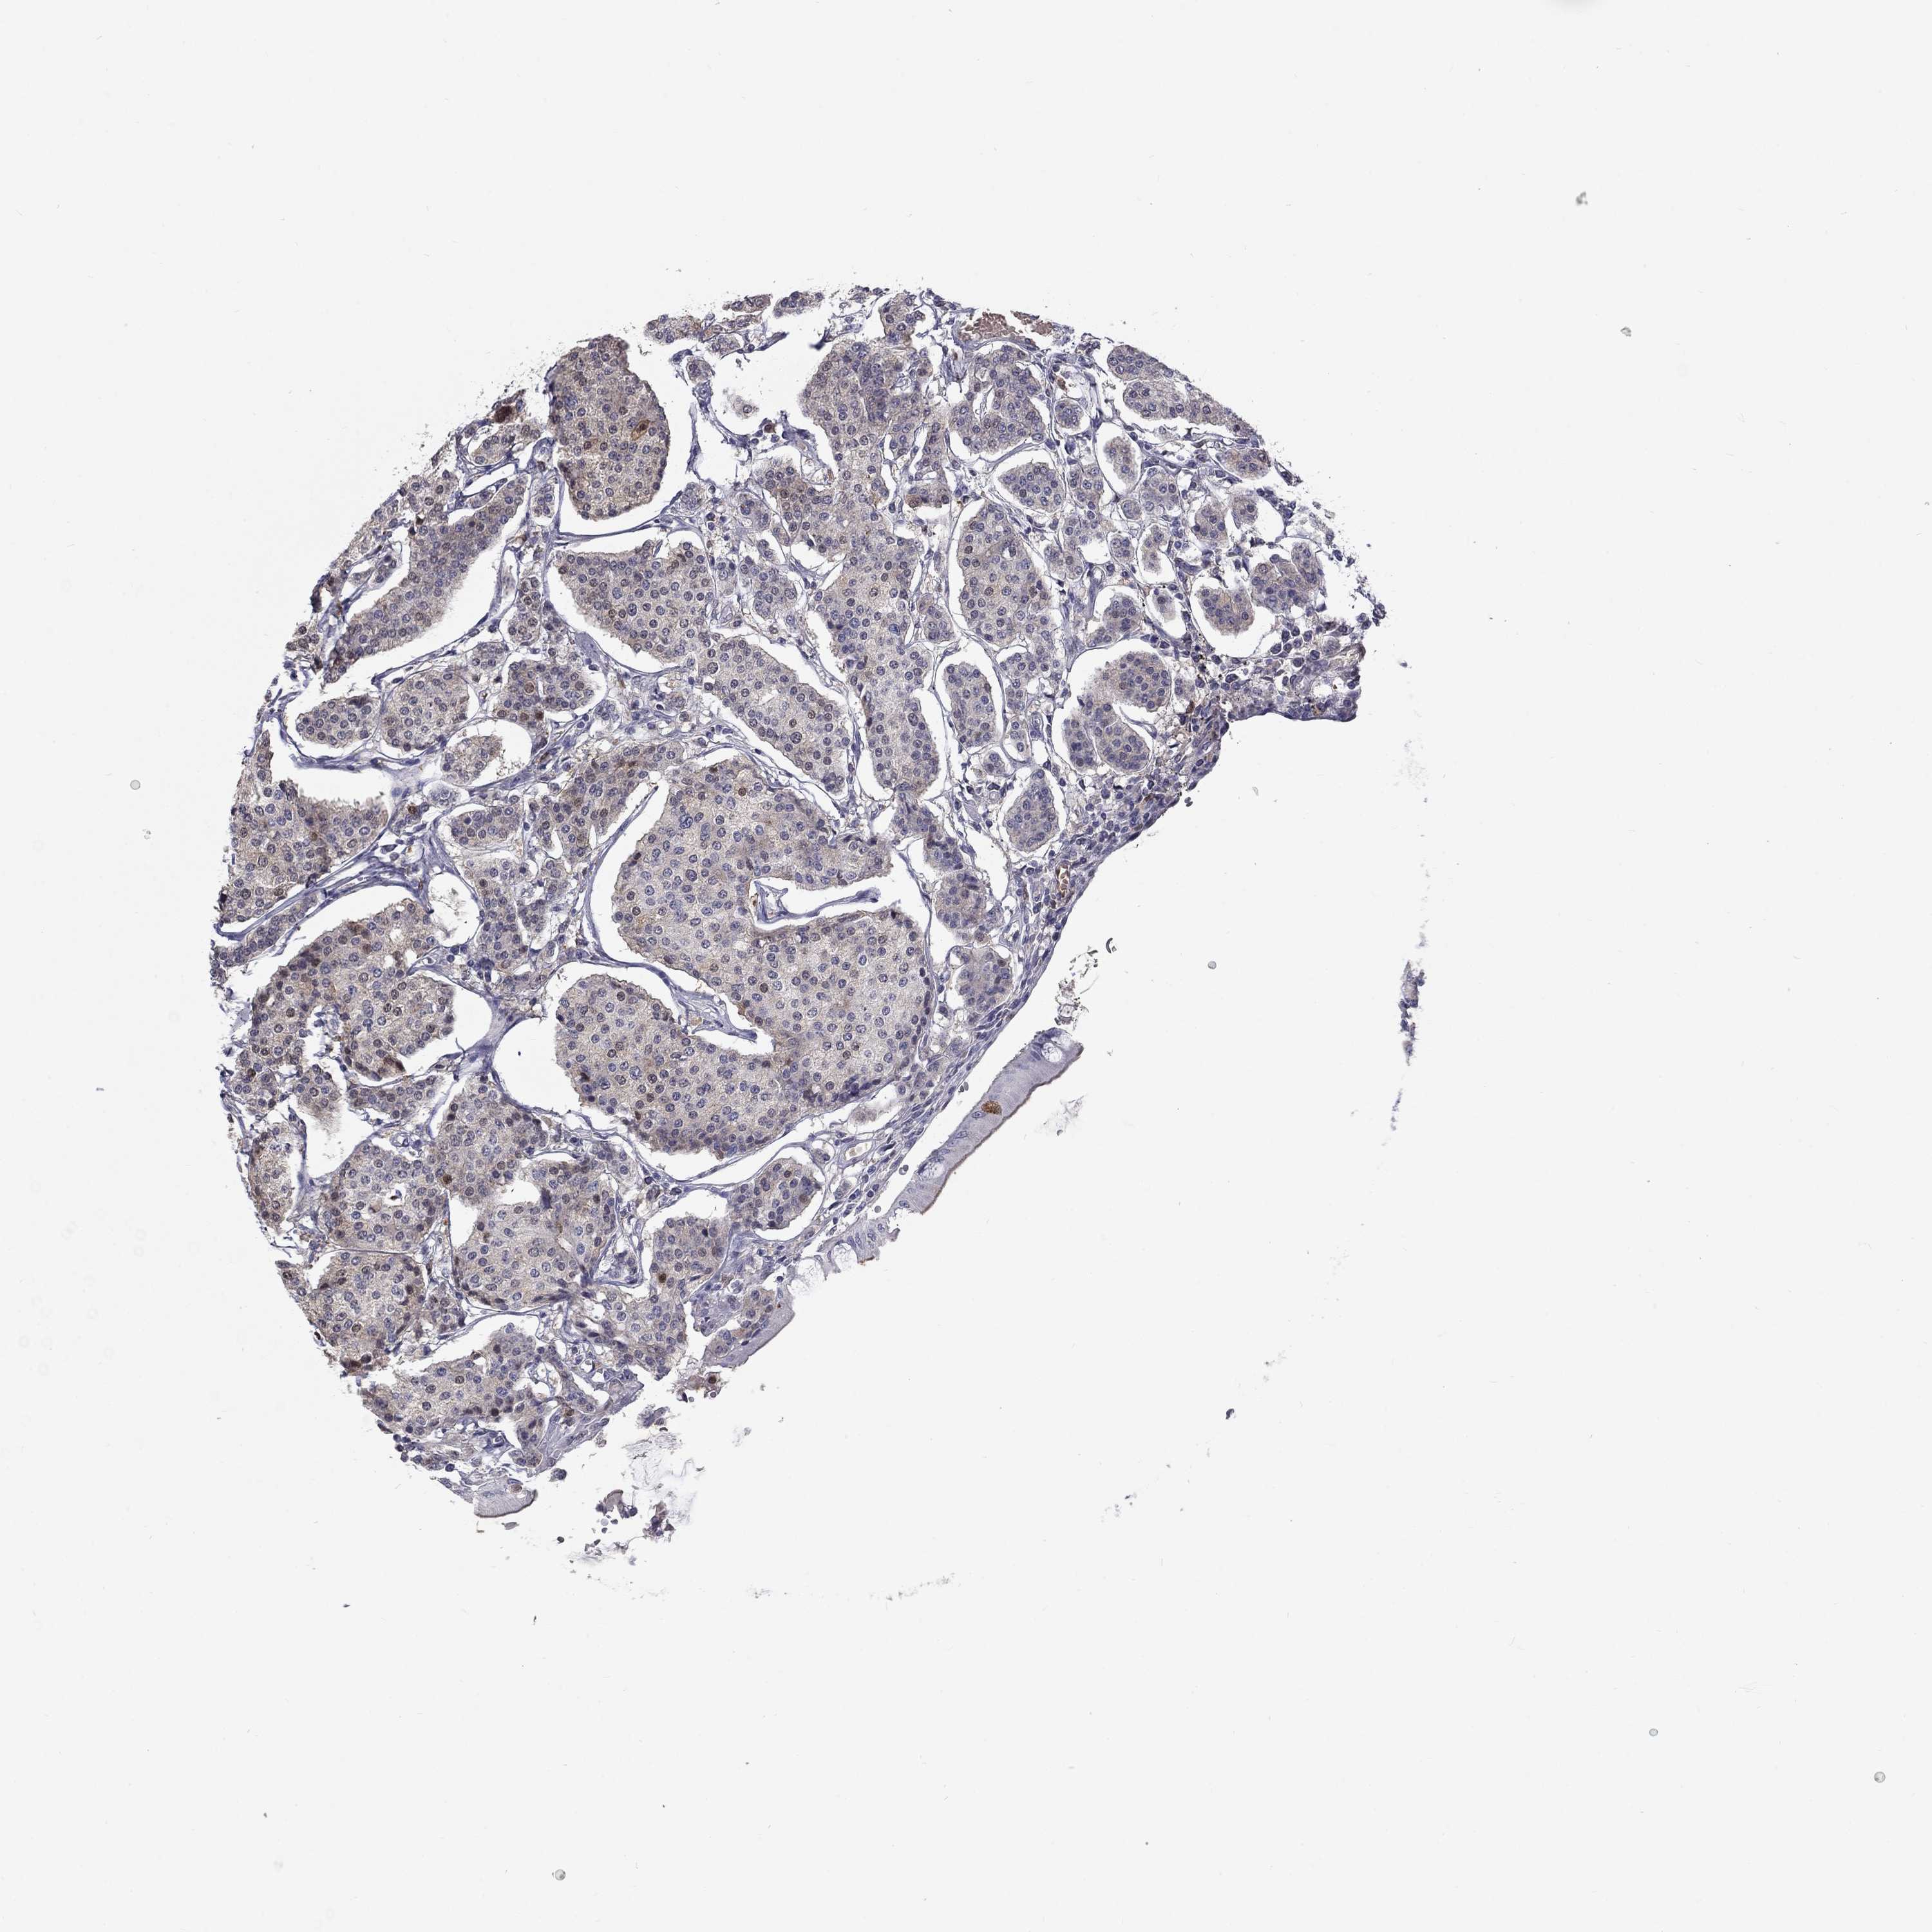

CARCINOID - Protein expressioni

A mouse-over function shows sample information and annotation data. Click on an image to view it in a full screen mode. Samples can be filtered based on level of antibody staining by selecting one or several of the following categories: high, medium, low and not detected. The assay and annotation is described here.

Each image is clickable and will lead to virtual microscopy that enables deeper exploration of all samples and also displays staining intensity scores, fraction scores and subcellular localization as well as patient and tissue information for each sample.

Antibody HPA011887

Carcinoid, malignant, NOS